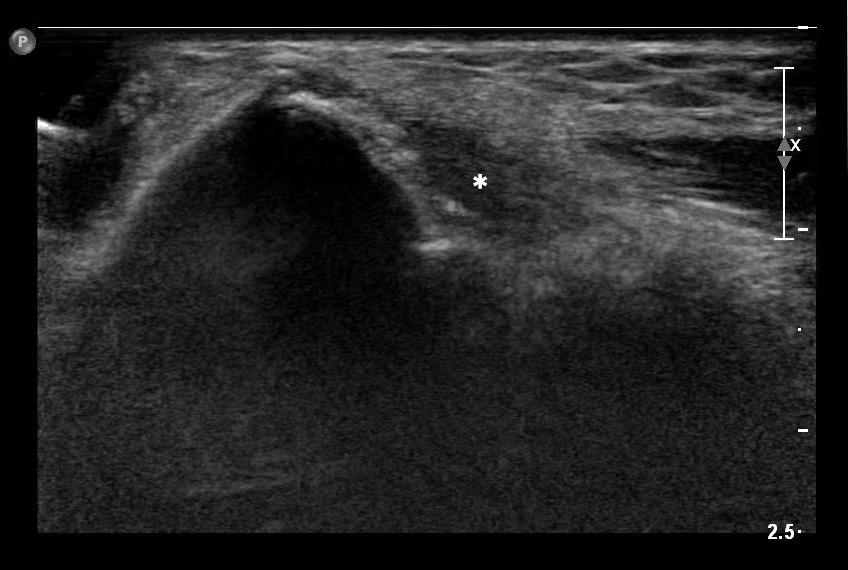

典型网球肘的超声表现为:肱骨外上髁处伸肌总腱增厚,止点处可见钙化,内部分布欠均匀,纤维纹理局部中断,内部血流信号增多,严重者存在积液。

在超声图像中,具体的表现为可以看到患者的伸肌总腱增厚,回声减低(*标记处)。